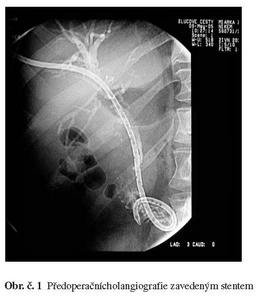

Autoři uvádějí kazuistiku 48 letého pacienta, který byl léčen pro ikterus vzniklý na podkladě stenózy žlučovodu typu Bismuth IV v hilu jater.

Nález byl chirurgem na jiném pracovišti vyhodnocen jako inoperabilní, z provedené peroperační biopsie nebyl histologicky karcinom potvrzen, přesto byla provedena brachyterapie cestou PTD, při které byla rovněž zavedena trvalá zevní drenáž jater. Na CT vyšetření je zřejmá atrofie levého laloku jater v důsledku postižení a uzávěru levé portální žíly. Obr. č. 2,3.